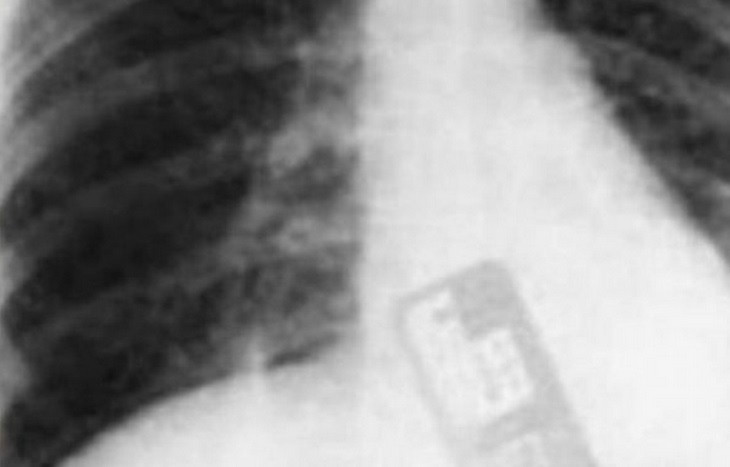

Un nuevo caso de negligencia médica fue dado a conocer, tras haberse sometido a una operación cesárea, Hannan Mahmoud Abdul Karin de 36 años tuvo que ser intervenida de emergencia tras comprobarse que dentro de su abdomen se encontraba el teléfono celular del ginecólogo que trajo al mundo a su hijo, esto luego de tomarse unas radiografías.

La mujer de Jordania tuvo que ser ingresada de urgencia en un hospital privado de Amman, ya que según explicó, comenzó a sentir vibraciones dentro de su abdómen y un dolor intenso, Hanan dió a luz un varón el pasado 24 de abril, durante su estadía en la maternidad mencionó que no se sintió mal y fue dada de alta, sin embargo en su hogar comenzó a experimentar intensos dolores en su vientre.

El ginecólogo jordano que la operó, dijo que dejó accidentalmente su teléfono celular en el abdomen de su paciente durante la cesárea, sin embargo a pesar de sus disculpas, está acusado de negligencia médica, ya que sus colegas y el mismo hospital indicaron a la policía jordana que el objeto olvidado durante la cirugía, pudo haberle costado la vida a la paciente y en el menor de los casos dejar infértil a la mujer.